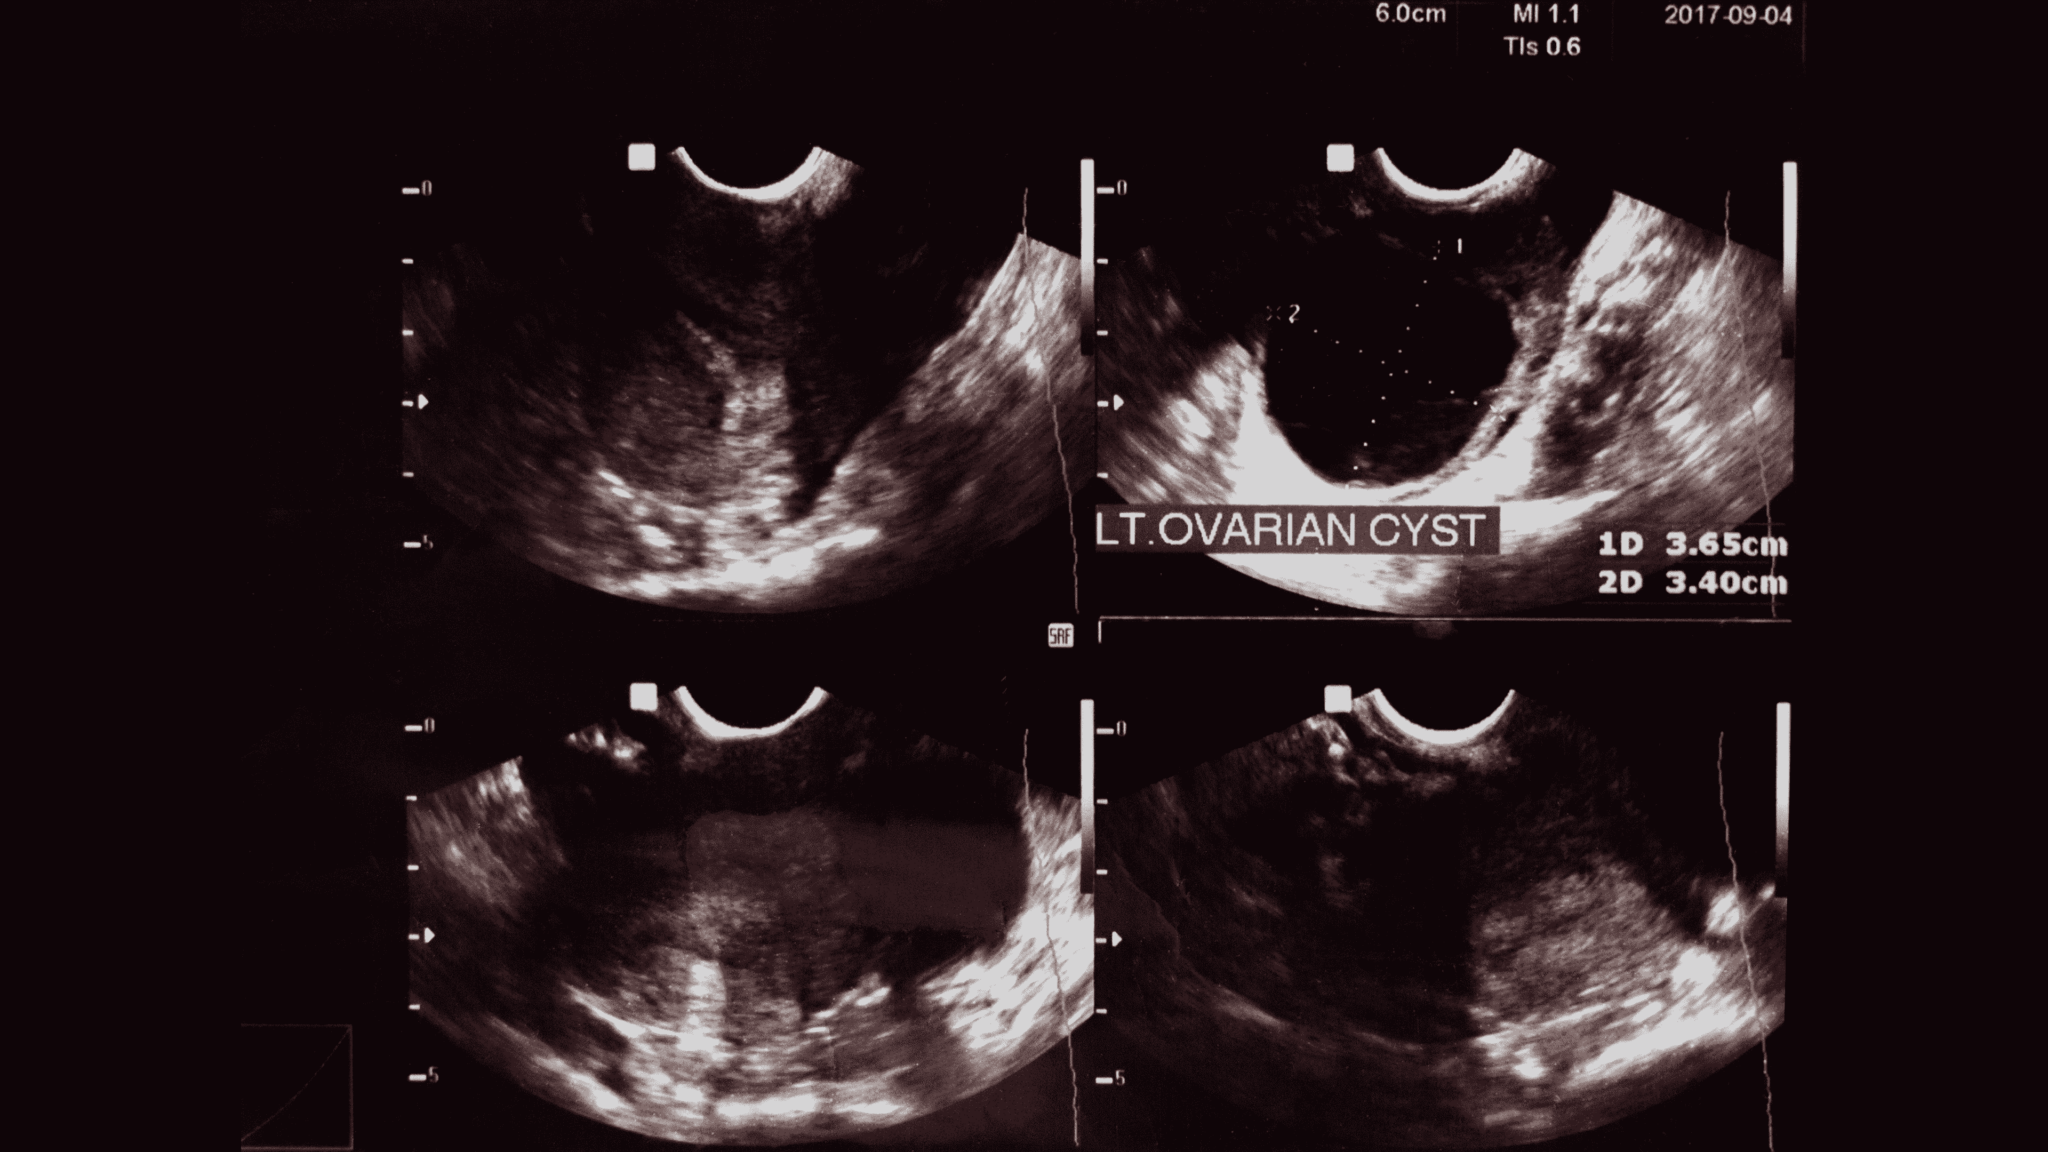

Discover essential facts about a complex cyst on ovary, including common symptoms, potential health risks, and diagnosis methods. Learn when to seek medical advice, how imaging tests like ultrasounds help identify suspicious growths, and why professional evaluation is vital for managing pelvic pain or ovarian health concerns effectively. Understand your treatment options for ovarian cysts today.